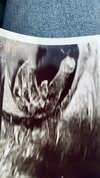

Witam przyszłe Mamy! Mam pytanko, jestem w 18 tyg ciąży.. tydzień temu lekarz prowadzący ciąże określił płeć na chłopca, czy jest szansa patrząc na to zdjęcie, żeby z tego koleżki zrobiła się jeszcze koleżanka? 🤣😜

• 5D78DFF2-1048-4185-AAE1-7C948B091760.jpeg